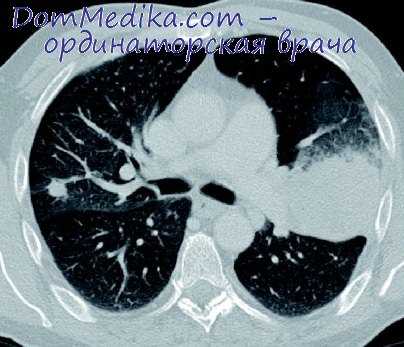

Верхняя лобэктомия справа

Легкое оттягивают кзади, диафрагмальный нерв берут на держалку. После двойного лигирования верхней легочной вены лигируют и пересекают V1 и V2 + V3. Затем выполняют перевязку и пересечение переднего ствола легочной артерии спереди, под непарную вену заводят держалку и отводят вену назад, после этого выполняют лигирование и пересечение A3 и А1 + А2. После лигирования и выделения легочной артерии берут на держалку бронх верхней доли легкого и завершают процедуру наложением шва. Выделяют область вокруг бронха, держалку проводят через нижнюю щель и отделяют клипсоап-пликатором. Важно отметить, что выделение бронха выполняют вместе с лимфодиссекцией.